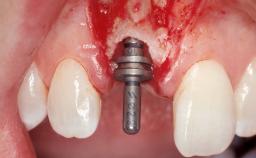

A 30-year-old female patient had lost tooth 21 and was referred to our clinic for consultation and treatment. Due to advanced apical infection, tooth 21 had been extracted two months earlier at another clinic and an acrylic-resin tooth had been bonded to the adjacent teeth. The patient desired implant treatment to avoid any damage to the adjacent natural teeth. While the patient had no history of any systemic disorder, she was a heavy smoker and exhibited medium to advanced periodontitis in the entire jaw. After the initial treatment to achieve a pocket probing depth of less than 4 mm and no bleeding on probing, a decrease in the height of the papillae mesial and distal to the extraction site and overall gingival recession were observed.

Bone Augmentation Horizontal|Staged

Augmentation Materials Autogenous chips|Membrane

Soft Tissue Grafting Simultaneous

Bone Volume Deficient horizontally, requiring prior grafting